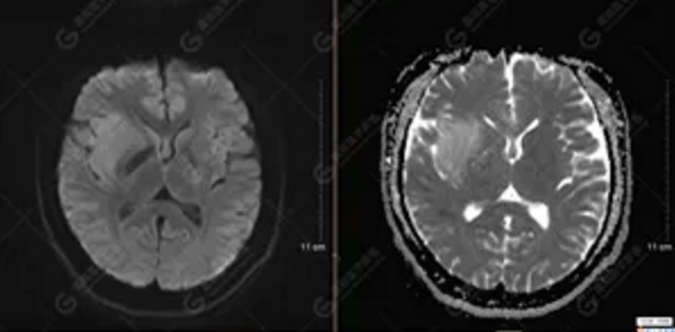

【MRI平掃及增強檢查所見】右側(cè)額顳島葉、右側(cè)海馬及右側(cè)基底節(jié)區(qū)見一團(tuán)塊狀異常信號影,累及右側(cè)下丘腦及視交叉,大小約5.1cm×4.5cm×4.3cm,呈長T1長T2信號,F(xiàn)LAIR序列呈等、稍高信號,DWI序列呈稍高信號,ADC圖高信號,增強后無明顯強化;病灶周圍見片狀長T1長T2水腫信號影,F(xiàn)LAIR序列呈高信號,病灶內(nèi)見右側(cè)大腦中動脈穿行。余腦實質(zhì)內(nèi)未見局灶性信號異常,增強后未見異常強化。右側(cè)側(cè)腦室輕度受壓,余腦室、腦池大小、形態(tài)均正常,中線結(jié)構(gòu)居中